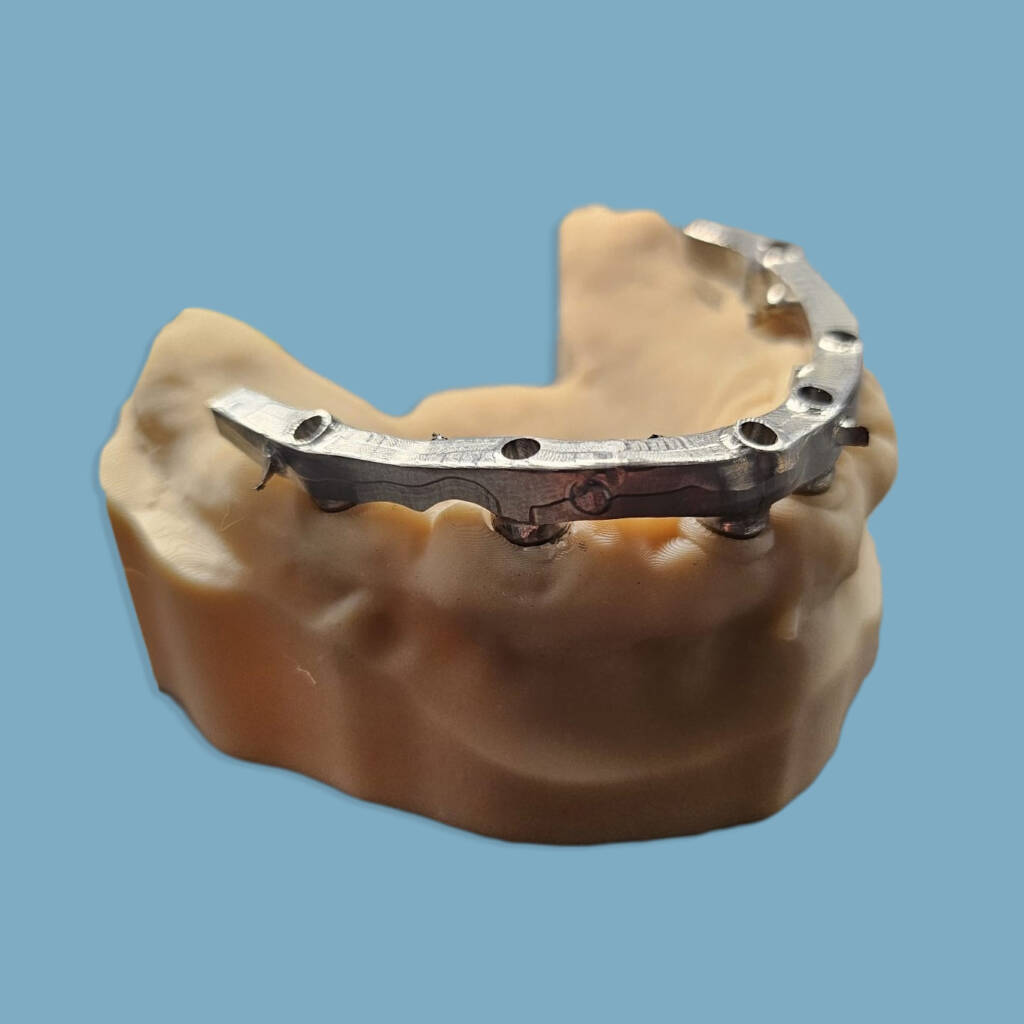

Expertise et polyvalence dans les systèmes implantaires et types de connectiques : hexagonales, internes ou externes. Notre savoir-faire englobe une large gamme de réalisations : couronnes, bridges, piliers implantaires, mises en charge immédiates et finitions sur barres implantaires. Nous travaillons divers matériaux comme le chrome-cobalt, le titane, la zircone pour garantir des solutions durables et sur mesure.

Implantologie conjointe